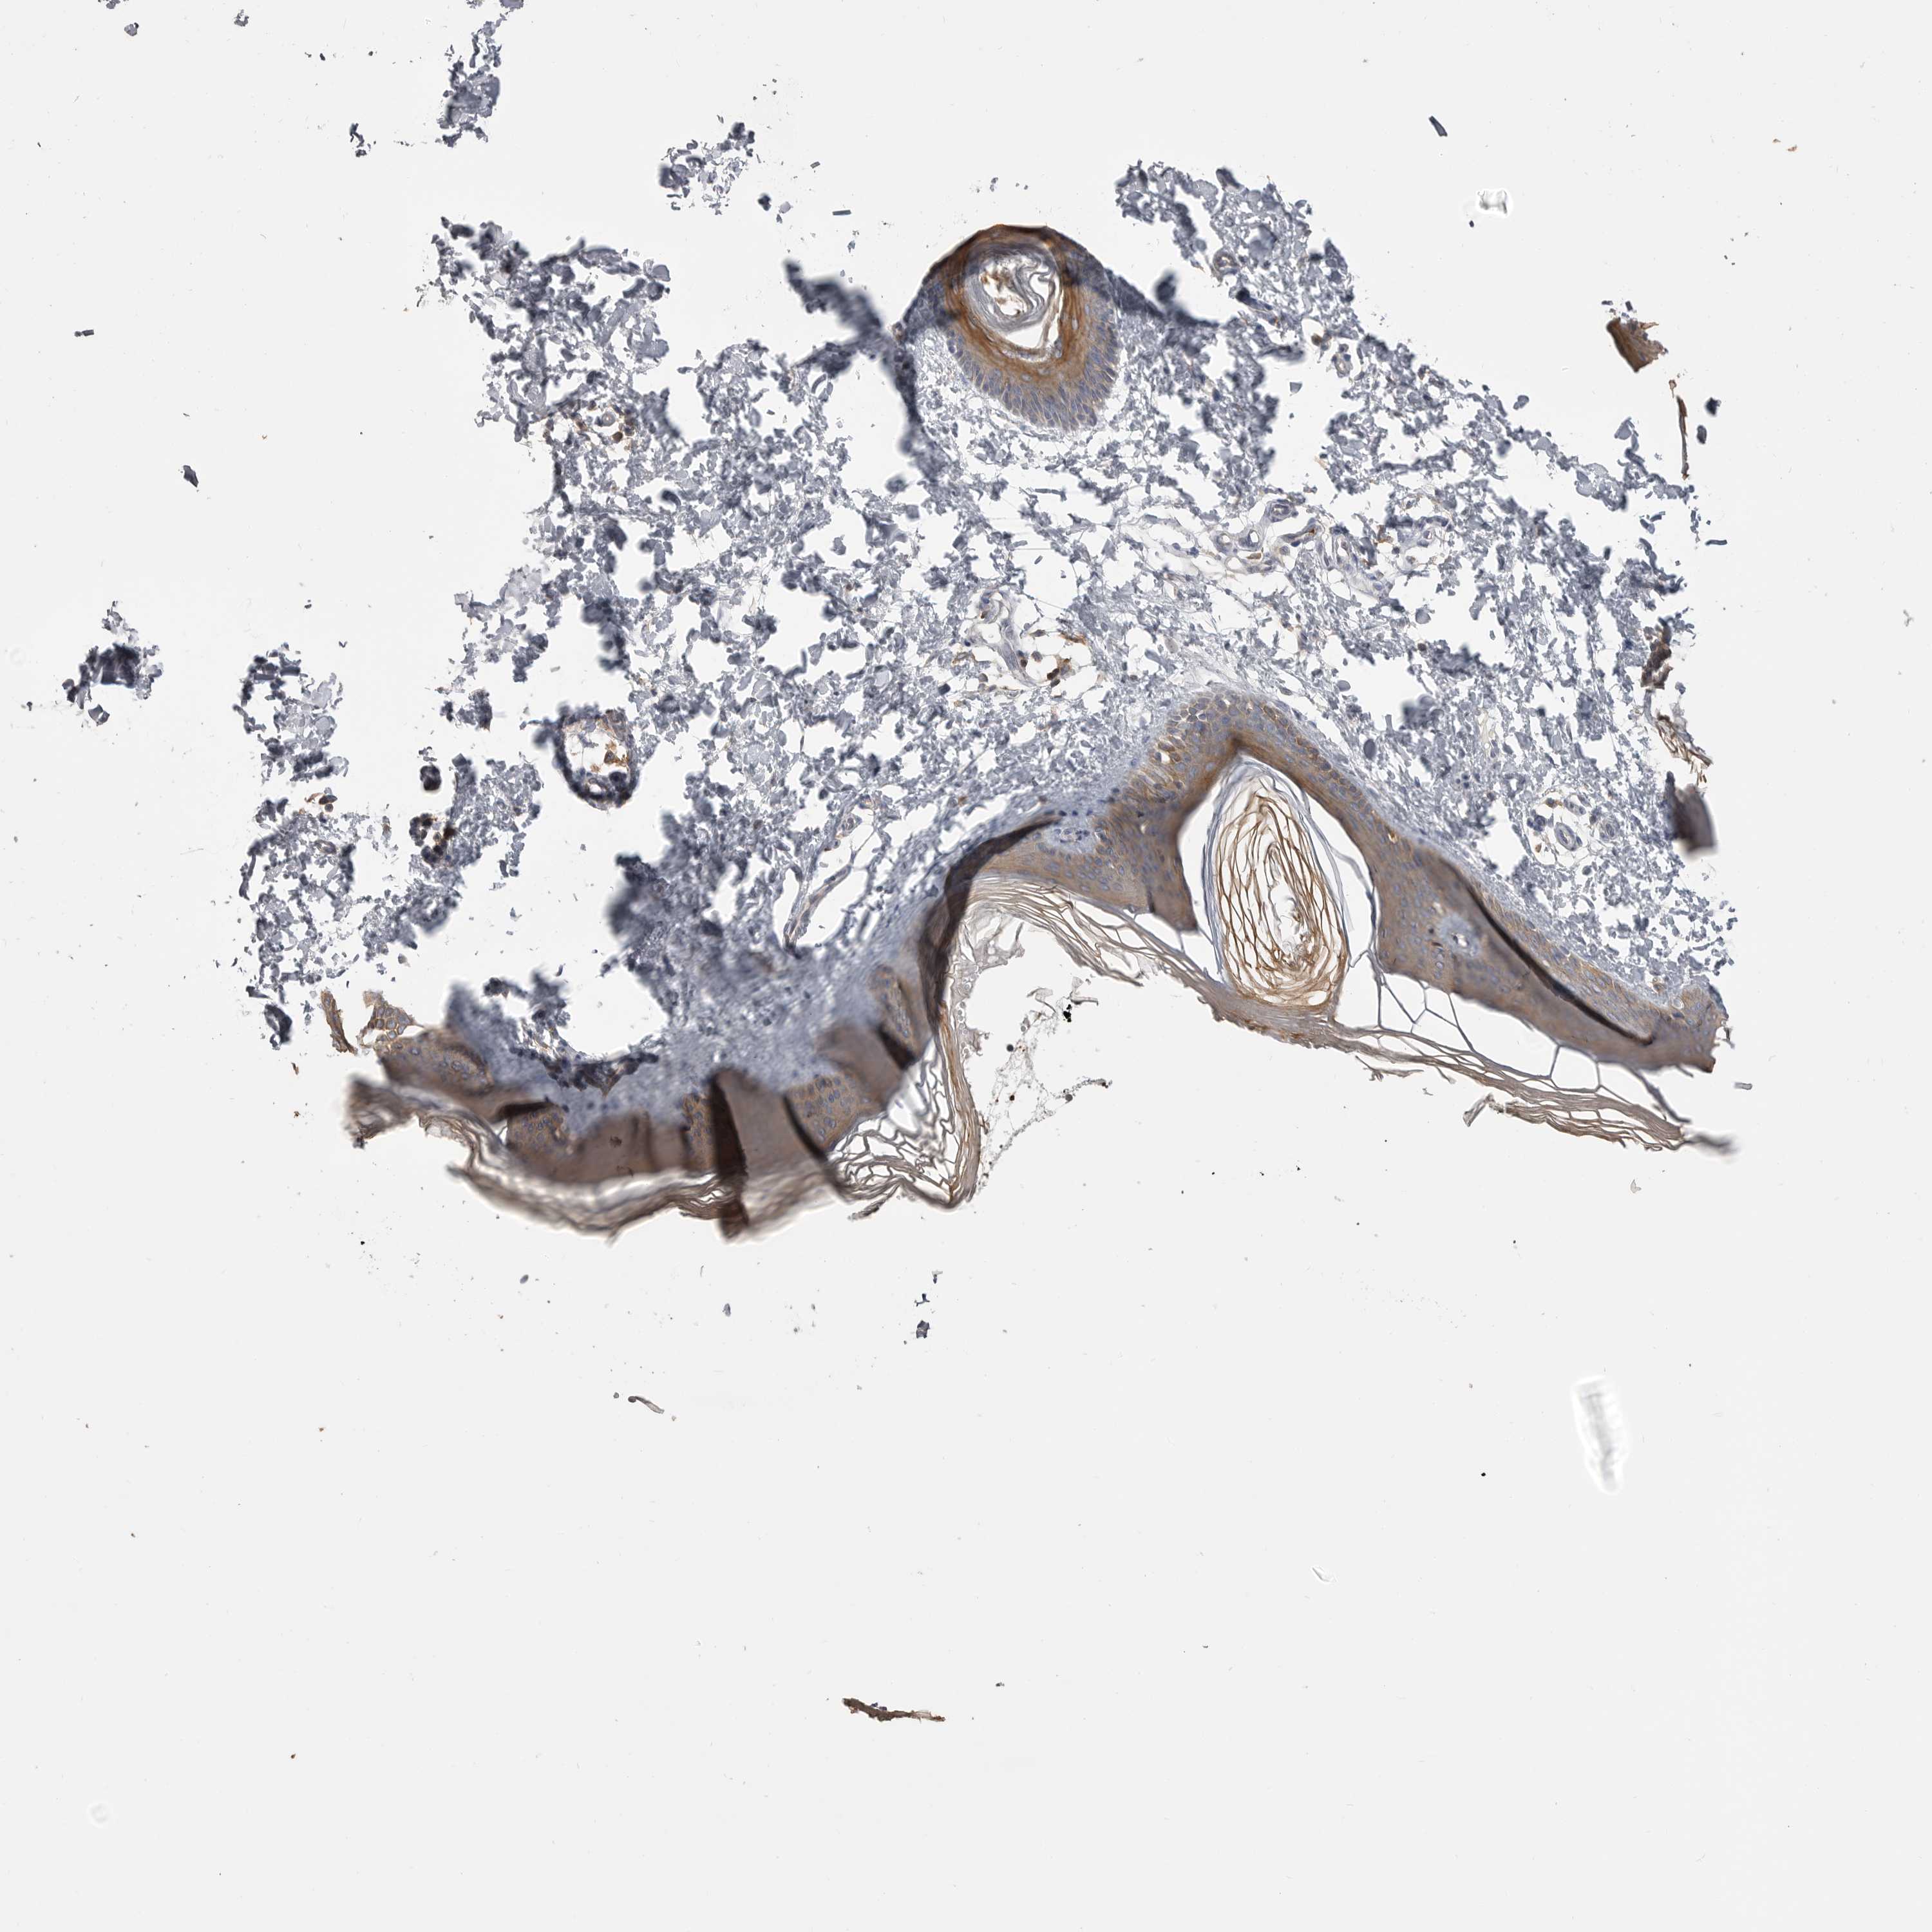

SKIN 1 - Antibody stainingi

Antibody staining in the annotated cell types in the current human tissue is reported as not detected, low, medium, or high, based on conventional immunohistochemistry profiling in selected tissues. This score is based on the combination of the staining intensity and fraction of stained cells. Each image is clickable and will lead to virtual microscopy that enables deeper exploration of all samples and also displays staining intensity scores, fraction scores and subcellular localization as well as patient and tissue information for each sample.

Antibody HPA026980

Langerhans Not detected

Fibroblasts Not detected

Keratinocytes Medium

Melanocytes Not detected